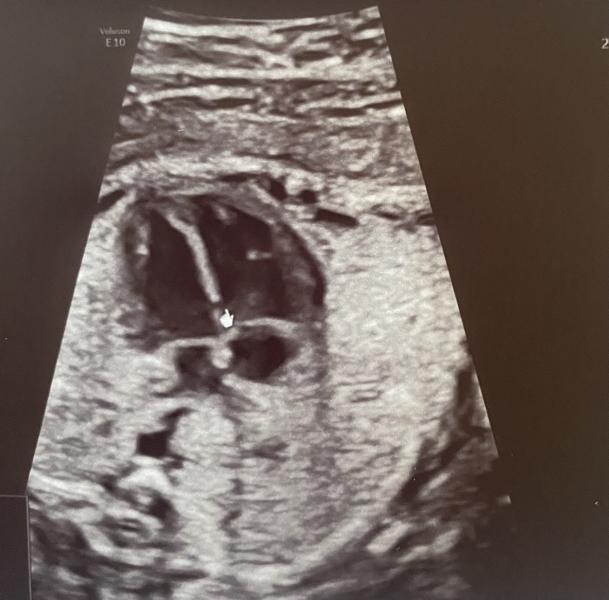

ДМЖП-дефект межжелудочковой перегородки 1,8 мм…вот с таким диагнозом вышла с 3Д узи, на которое записалась ради интереса (очень уж на свою крошку хотела полюбоваться). Полюбовалась…от услышанного упала в обморок прямо лёжа на кушетке врача. Плачу который день, не нахожу себе места, перечитала кучу информации, все настолько противоречиво, что не знаю, чему верить. Девочки, у чьих малышей был подобный диагноз, расскажите, что это, как с этим быть, как с этим жить.

Просто написали, что это ВПР-врождённый порок сердца. Диагноз просто землю из-под ног выбивает. Звучит безумно страшно.